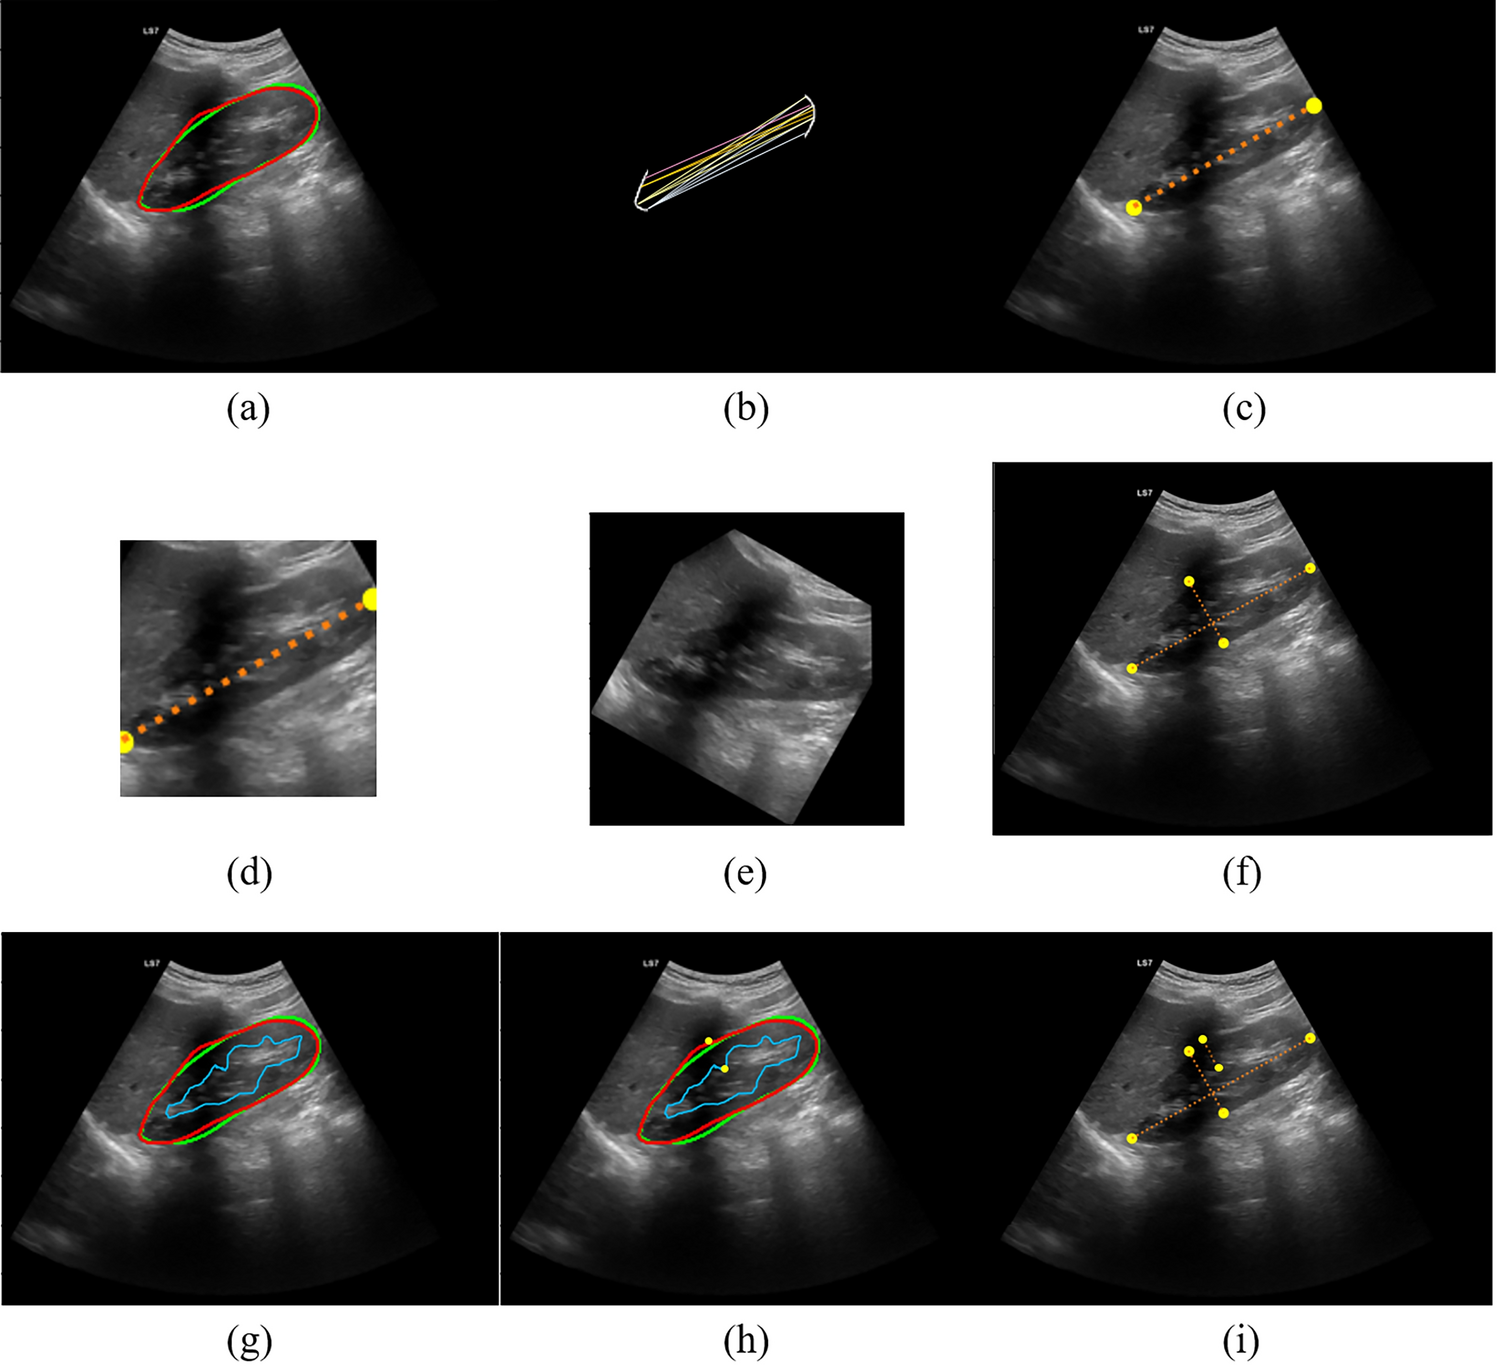

Figure 2

From: Fully automated kidney image biomarker prediction in ultrasound scans using Fast-Unet++

Post-processing of sagittal view image. (a) Segmentation of the capsule. The ground truth is the green contour and the predicted mask is the red one. (b) Finding the farthest pairs of points between two poles, (c) kidney length (KL), (d) tailored crop, (e) rotation of the image to make it horizontal, (f) finding kidney thickness, (g) segmentation of sinus, (h) finding the farthest pairs of points between sinus and capsule’s masks, and (i) parenchyma length.